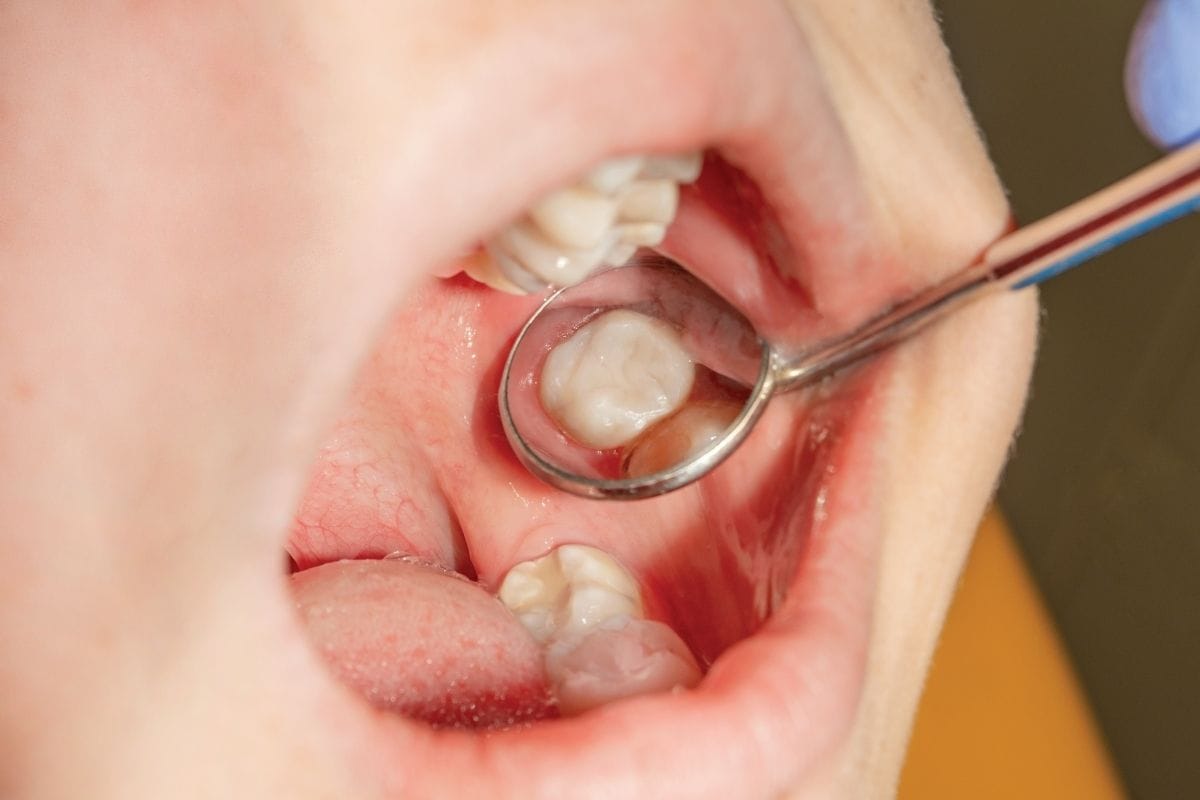

Diş çürükleri, kırıklar, travmalar ya da estetik nedenlerle zamanla yıpranan dişler, hastaların hem sağlık hem de görünüm açısından şikayetçi olduğu başlıca sorunlardandır. Restoratif diş tedavisi, çeşitli nedenlerle hasar görmüş diş dokusunun eski formuna kavuşturulması için uygulanan tedavi yöntemlerini kapsar.

Bu tedavi sayesinde hem dişin estetik görünümü korunur hem de çiğneme, konuşma gibi temel fonksiyonlar yeniden kazandırılır. Özellikle kompozit dolgu, inley/onley uygulamaları, porselen kaplamalar ve implant üstü restorasyonlar, bu tedavi alanının öne çıkan uygulamaları arasındadır.